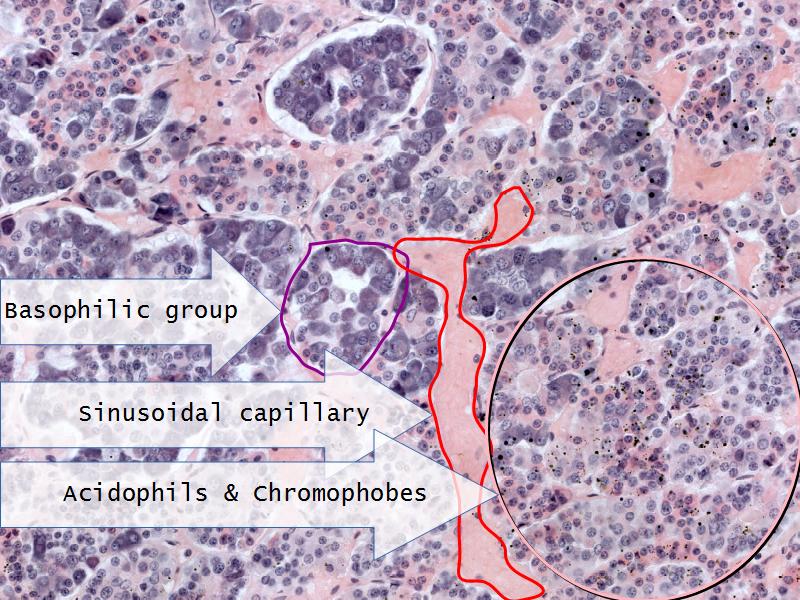

- E1: ACTH = basophils in the pituitary gland

- Slide 52: Pituitary gland

Pituitary gland

How does the pituitary and hypothalamus communicate?2 ways